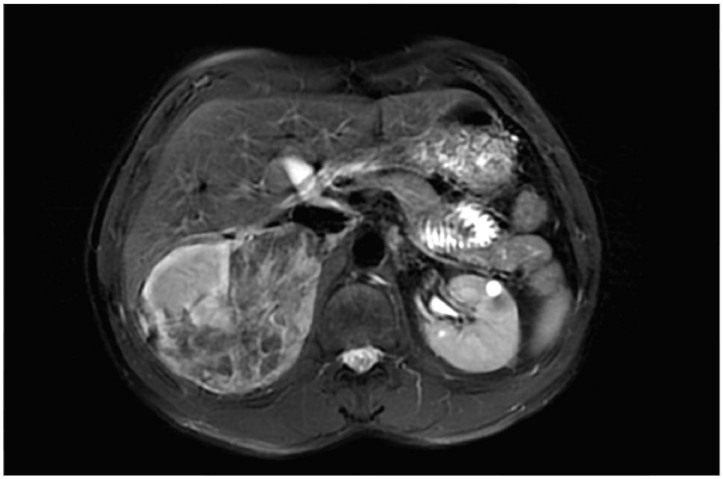

Tuberous sclerosis complex (TSC) is an autosomal dominant disease characterized by the development of hamartomas in the central nervous system, heart, skin, lungs, and kidneys and other manifestations including seizures, cortical tubers, radial migration lines, autism and cognitive disability. The disease is associated with pathogenic variants in the TSC1 or TSC2 genes, resulting in the hyperactivation of the mTOR pathway, a key regulator of cell growth and metabolism. Consequently, the hyperactivation of the mTOR pathway leads to abnormal tissue proliferation and the development of solid tumors. Kidney involvement in TSC is characterized by the development of cystic lesions, renal cell carcinoma and renal angiomyolipomas, which may progress and cause pain, bleeding, and loss of kidney function. Over the past years, there has been a notable shift in the therapeutic approach to TSC, particularly in addressing renal manifestations. mTOR inhibitors have emerged as the primary therapeutic option, whereas surgical interventions like nephrectomy and embolization being reserved primarily for complications unresponsive to clinical treatment, such as severe renal hemorrhage. This review focuses on the main clinical characteristics of TSC, the mechanisms underlying kidney involvement, the recent advances in therapy for kidney lesions, and the future perspectives.